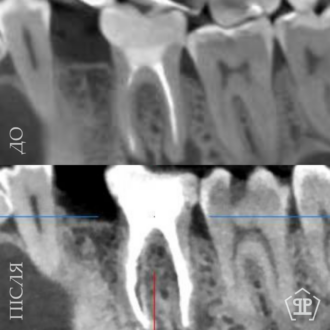

Роботи лікаря Все работы ⋅⋅⋅